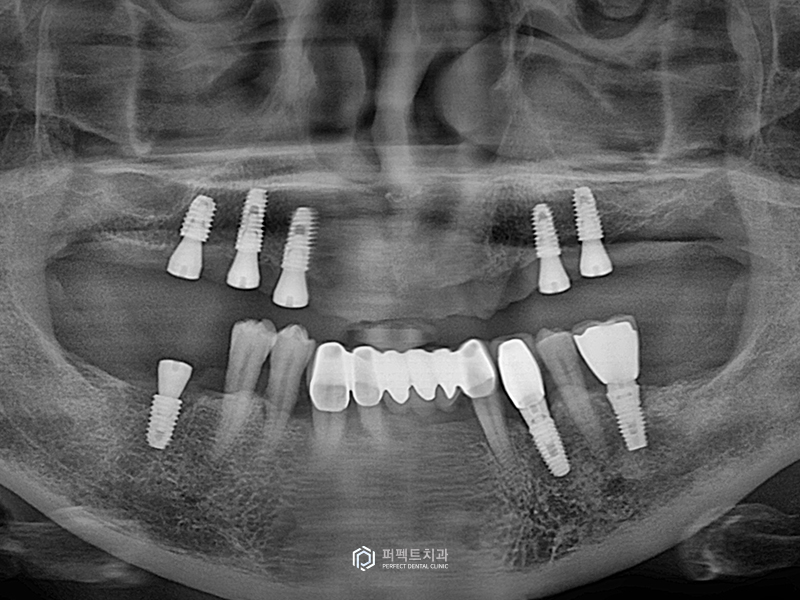

오른쪽 3개, 왼쪽 2개의 임플란트를 식립한 후의 사진입니다. 말씀드린 것처럼 앞 부분에는 임플란트를 식립할 수 없는 경우였고, 조금 아쉬운 점은 뒷 부분에 상악동 수술을 하여 임플란트를 더 심어주면 좋은데 환자분이 원하지 않으셔서 임플란트를 식립한 부분까지만 기능을 할 수 있도록 해드렸습니다.

총 수술 시간은 20분 이내로 비교적 간단하게 마무리 할 수 있었습니다. 또한 사진을 보시면 알 수 있듯이 절개한 흔적도 보이지 않는 것을 알 수 있습니다.

엑스레이 사진을 보시면 상악동은 건들지 않고 수술을 했습니다.

잇몸을 열지 않고 수술을 하기 때문에 보지않고 수술을 하는 것과 똑같은데, 이렇게 할 수 있는 이유는 가이드를 이용해서 수술을 하기 때문에 원하는 길이와 정확한 위치에 식립할 수 있기 때문입니다.